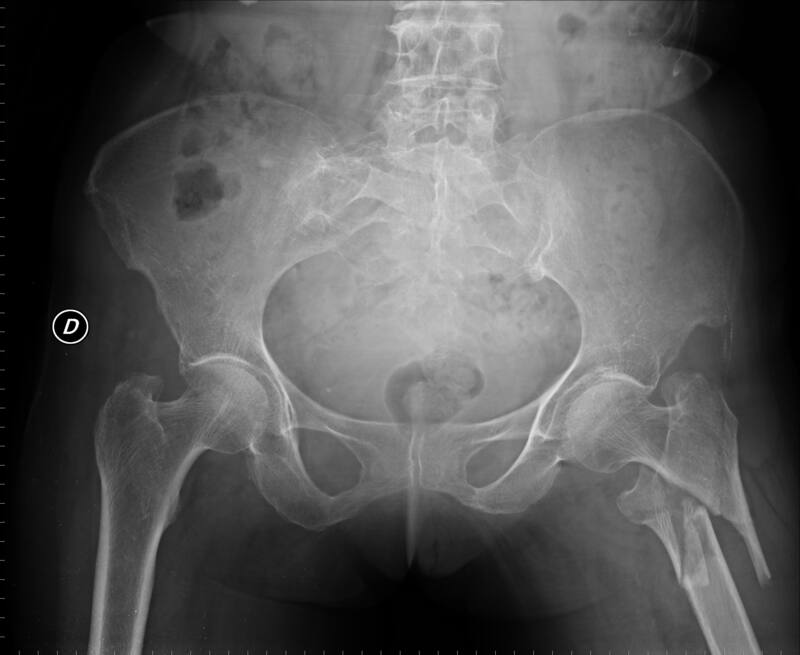

El doctor canadiense Peter Attia, reconocido especialista en longevidad, no oculta la cruda realidad: "Si te rompes el fémur o la cadera a partir de los 65 años, tienes entre un 15% y un 30% de probabilidades de morir en un año". Una cifra aterradora que invita a actuar desde ya.

Un estudio publicado por el World Journal of Orthopedics revela que alrededor del 22% de los mayores de 60 años fallecen al año tras una fractura de cadera. En España, esa tasa se sitúa entre el 20% y el 23%.

No todas las fracturas tienen el mismo pronóstico. Hay estudios que elevan esa mortalidad al 27% en el primer año entre mayores de 65, especialmente si hay enfermedades cardíacas, demencia o complicaciones postoperatorias.